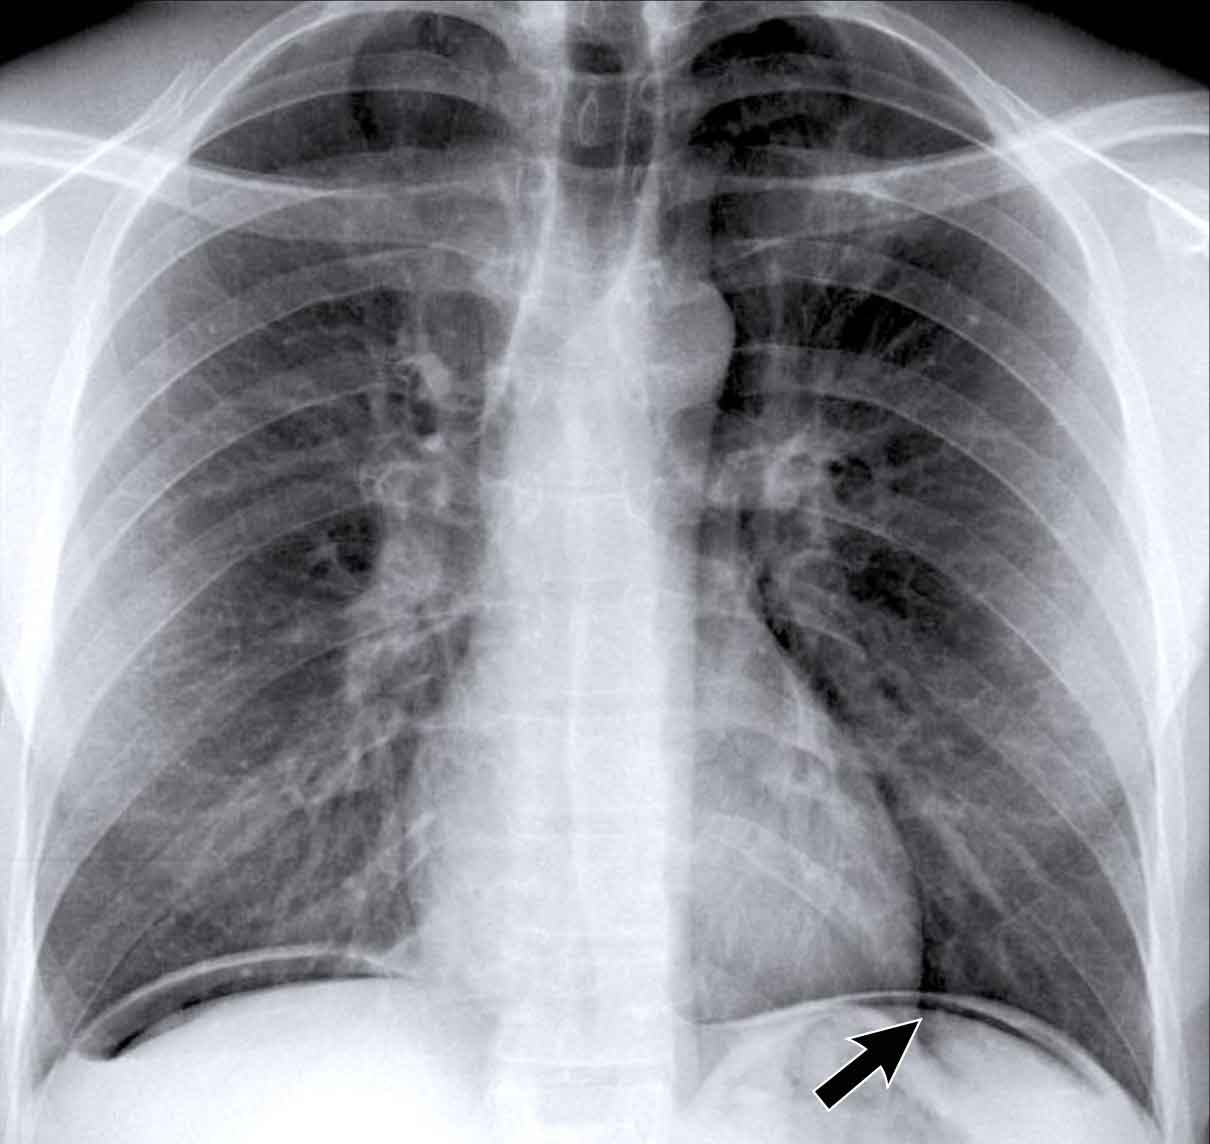

Pericardial cyst

Pericardial cysts are benign lesions that are anatomically connected to the pericardium and typically contain clear, serous fluid.

The majority of pericardial cysts are located in the anterior cardiophrenic angle, more frequently on the right side.

However, they may also be identified more superiorly, within the pericardial recesses at the level of the proximal ascending aorta and main pulmonary arteries.

Most patients remain asymptomatic.

On chest radiography, a pericardial cyst may mimic an elevated left hemidiaphragm (black arrow).

However, CT more clearly demonstrates a fluid-filled cystic lesion contiguous with the pericardium (yellow arrow).